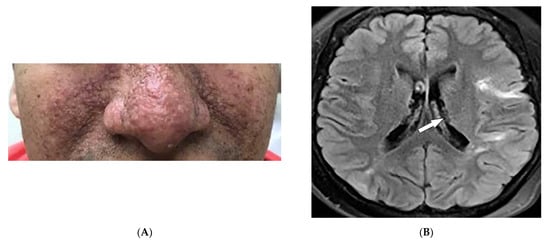

| Kaposi sarcoma | Erythematous or violaceous macules, plaques, nodules Pulmonary involvement Gastrointestinal involvement | Nodular enhancing masses Peribroncovascular nodules and halo sign |

4.2. Kaposi Sarcoma